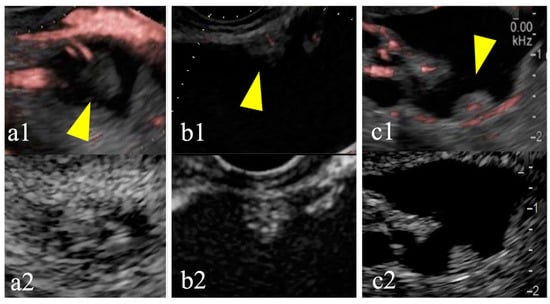

Figure 1. Mucus clots are difficult to differentiate from mural nodules. Case 1: a mural lesion in a cyst observed using conventional B-mode imaging (a1) exhibiting no enhancement (yellow arrow) (a2), thus leading to a diagnosis of a mucus clot. Case 2: a mural lesion in a cyst observed using conventional B-mode imaging (b1) exhibiting enhancement during imaging (yellow arrow) (b2), thus leading to a diagnosis of a mural nodule.